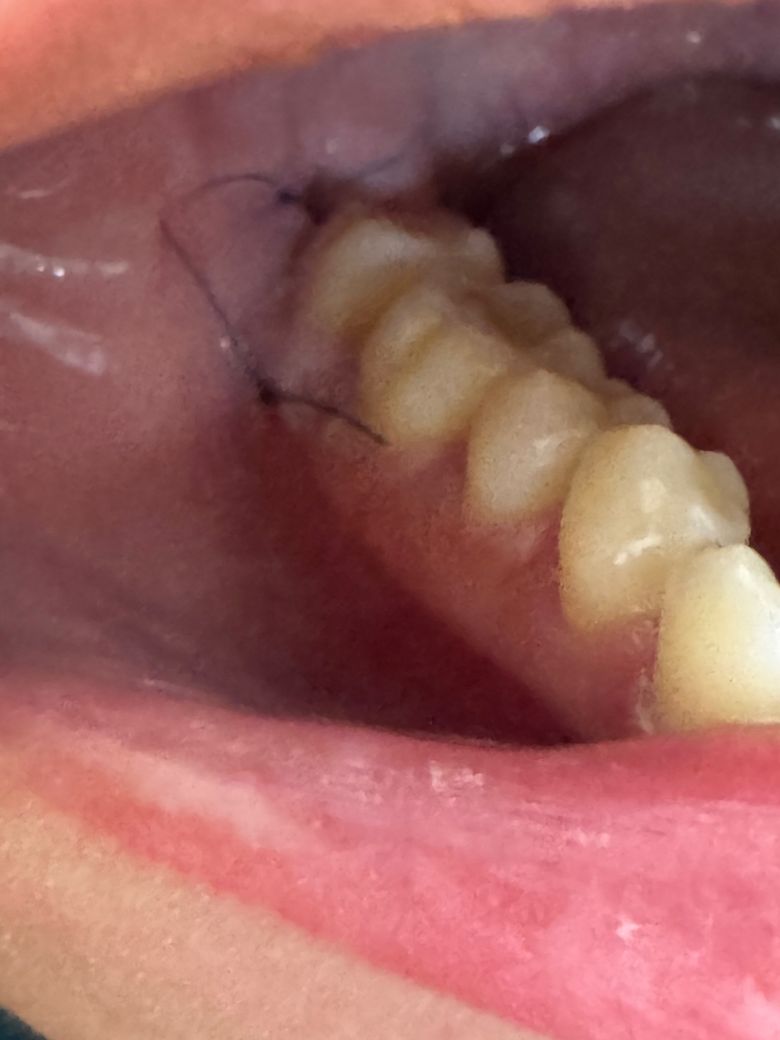

사랑니 5일차 실밥 괜찮은건가요??

매복 사랑니 발치하고 5일째인데 저녁식사 끝 무렵쯤에 갑자기 발치한 쪽에 이물감이 많이 느껴져서 확인해 보니 실밥이 평소보다 혀에 많이 닿고 좀 풀어진 느낌이 있었어요

몇 시간 만에 갑자기 입도 잘 벌어지고 뻐근함도 덜해졌는데 실밥이 풀린 걸까요?

좀 불편하고 많이 거슬리는데 치과에 가봐야 할까요?

현재 처방받은 소염진통제 약은 오늘로써 다 복용한 상태이고 실밥 풀기로 예약된 날까진 4일 정도 남았습니다!

• 1번 째 사진

사랑니 뽑은 지 5일차이고 현재 잇몸 상태를 봤을 땐 원활하게 회복되고 있는 것으로 보입니다.

정상적으로 아물고 있는 것으로 보입니다. 원래 실밥 매듭이 긴 것인지 실밥이 풀린 것인지 사진에서는 구분 어렵습니다. 실밥 풀리거나 실밥 떨어져 나가도 문제없으니 예약한 날 가서 실밥 풀면 됩니다.

사랑니 발치를 한곳의 잇몸이 시간이 지나면서 붓기가 빠져서 실밥이 느슨해 진거 같습니다 .큰 문제가 잇는건 아닙니다

봉합실 끝쪽이 다소 길어서 걸리적 거릴 순 있는데 봉합이 완전히 풀어지거나 하진 않았습니다. 특별히 많이 불편하지 않으시다면 원래 실밥푸는날 가셔도 될 것 같습니다.